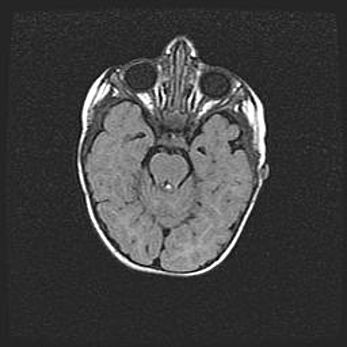

Лейкомаляция с кистозно-глиозной дегенерацией головного мозга.

Возраст: 2 месяца 25 дней

Вес: 6400 г

Окружность головы: 40 см

Срок гестации: 41 неделя

Лейкомаляцию относят к ишемически-гипоксическим повреждениям головного мозга, диагностируемым у новорожденных. При лейкомаляции в головном мозге обнаруживают очаги некроза, возникшие после тяжелой гипоксии и нарушения кровотока. В процессе морфогенеза очаги проходят три стадии: 1) развития некроза, 2) резорбции и 3) формирования глиозного рубца или кисты. Перивентрикулярная лейкомаляция (ПЛ) встречается примерно в 12% случаев среди новорожденных, обычно – у недоношенных детей, причем, частота ее зависит от массы, с которой младенец появился на свет. Наибольшее число малышей страдает лейкомаляцией, если масса при рождении 1500-2500 г.